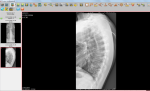

Открыты ли зоны роста на данных снимках

Здравствуйте, можно ли по данным снимкам определить открыты ли зоны роста? А также совпадает ли костный возраст с паспортным? Мой рост 174 см, Рост отца 176 см, рост мамы 158см. За год вырос на 3 см. Заранее спасибо.